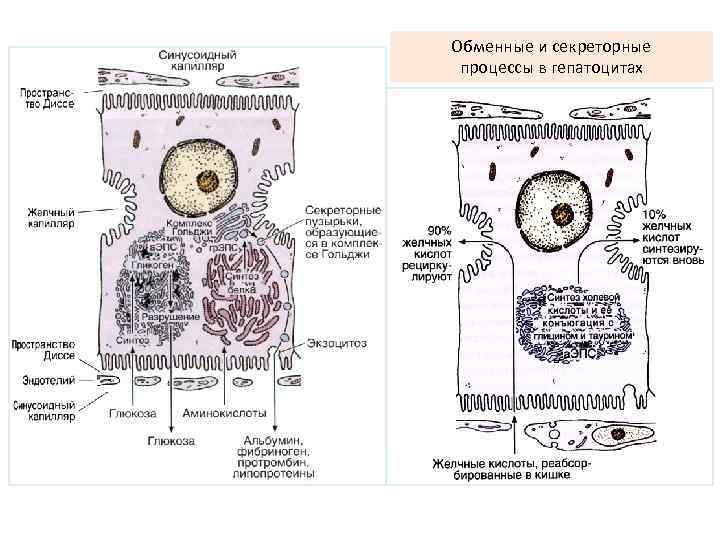

Обменные и секреторные процессы в гепатоцитах